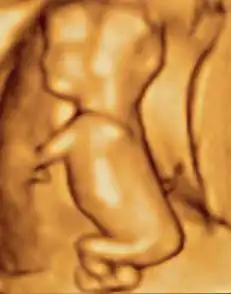

Fetus at 4+1⁄4 months